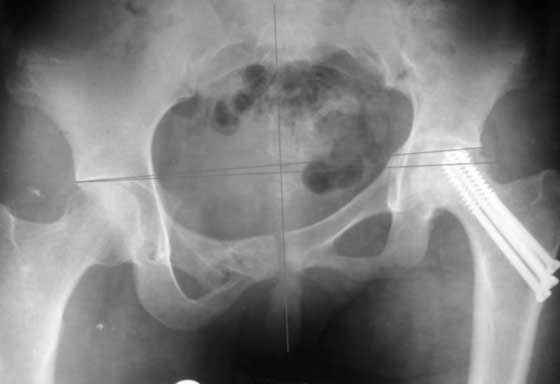

Re: AVN of femoral head and fracture of the pelvis.

До сих пор идут большие дискуссии по поводу высокого центра ротации и единого мнения, насколько я знаю, нет. Компенсация длины, рычагов ягодичных мышц и т.д., а уж при вертикальном смещении таза,влияние его на последующее эндопротезирование просто не узнать (слишком мало наблюдений и много факторов, влияющих на конечный результат). Фото лишний раз подтверждают, укорочение за счет контрактуры.